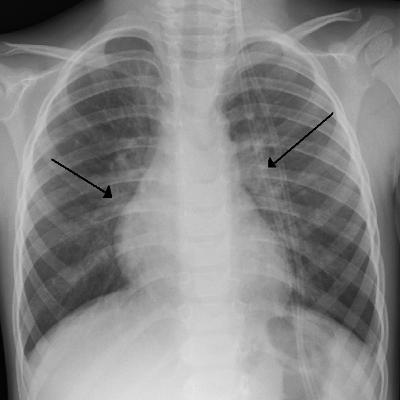

Pop quiz! What do you do if your child swallows a coin? Should you take them to the doctor, go to the ER, or just ignore it? Today, in his most ambitious video yet, Dr. Bee explains what you should do if your child swallows a coin, a battery, magnets, or any other item!